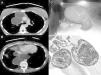

The patient is a 20-year-old woman, originally from Moldavia, who came to the emergency department in March 2011 complaining of sharp chest pain in the right anterior region that had been evolving over the course of the previous 2 months, along with mild dysphagia for both solids and liquids. Her medical history included the resection in Moldavia of a “lung parasite” by means of right thoracotomy in 2006, followed by one year of anti-parasitic treatment. Physical examination confirmed a scar from the right posterolateral thoracotomy and blood work showed mild anemia (Hb 11.7) with no leukocytosis or eosinophilia, with negative hydatid cyst serology. Imaging studies, including chest radiography, computed tomography (Fig. 1A and B) and magnetic resonance, revealed mediastinal widening due to the presence of multiple cystic mediastinal masses with affectation of the 3 compartments and craniocaudal extension, which produced a significant mass effect on the adjacent vascular structures and esophagus, with a minimal quantity of pericardial effusion. The liver presented no findings. Given the patient's history, we suspected mediastinal hydatidosis that was probably secondary, and right re-thoracotomy intervention was programmed. After the release of intense pleural adhesions, resection of the pericyst was initiated (Fig. 1C) with complete resection of all the cysts that had been observed by imaging techniques, using continuous lavage with hypertonic saline. The pericysts were resected, and those that could not be completely resected were left flat. The post-op period transpired without incident, and treatment was initiated with 400mg albendazole every 12h; the patient was released from the hospital after 7 days. Anatomic pathology and microbiology reports confirmed the presence of E. granulosus. With an optical microscope (Fig. 1D), the cystic capsule was able to be observed, which was made up of laminated membrane and germinal layer, with freed scolex. PCR detected nucleic acids of E. granulosus. To date (18 months later), there have been no symptoms or radiological signs of relapse.

(A and B) Computed tomography: axial slices obtained with mediastinal window showing a large multiseptated multicystic mass with linear enhancement extending in a craniocaudal direction. It affects the 3 mediastinal compartments and conditions the mass effect on adjacent vascular structures (superior cava in A and esophagus in B). (C) Entire hydatid obtained after opening the pericyst. (D) Image obtained by H–E 20× stain: hydatid cyst with laminated membrane and freed scolex; scolex with 4 suckers and rostellum with double crown of hooks.